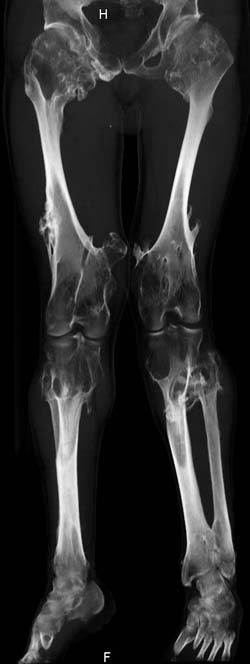

Oбратился больной 30 лет с хондродисплазией, множественными деформациями и экзостозами. Сгибательно-приводящие контрактуры Т/Б сустав, поясничный лордоз.

Интелектуально развит, работает програмистом. Болей нет. Анализы крови в пределах нормы, понижен кальций (общий Ca 1.62, N от 2.3 до 2.75;ионизорованный 0.67, N от 0.7 до 1.07) и щелочная фосфотаза -7.9. По данным КТ, оптическая плотность диафизов 150 - 200 NU (N в его возрасте 300 -350NU) метафизарный остеопороз от 100NU до отрицательных величин - 80 NU.

Больной настоятельно просит об исправлении деформаций и удаления экзостозов области коленных суставов.

30 years old male with chondrodysplasia and multiple exostoses admitted.Multilevel deformities, flexion-adduction limitation of hip ROM, lumbar lordosis. Intellectually developed, working in some software company. Painless. Blood tests are normal, except low Calcium (total serum Ca 1. 62, N is 2.3 - 2.75; ionized 0.67 N is 0.7 -1.07) and low alkaline phosphatase 7.9. Diaphysis bone density is about 150 - 200 NU (N in his age is 300 - 350NU). Metaphis osteoporosis is from 100NU to minus 80 NU.

The x-ray is satisfactory for analysis. In The AP view, The knee and ankle should be exactly anterior and the patella should be facing forward, then we can measure the deformity in the AP. Another lateral view of the whole lower limb should be taken, so we can correct 6 dimensions (X, Y and Z axes and Alpha, Beta and Gamma rotation).

But it seemes to me that he has distal femoral valgus and may be also distal tibial. But anyway, we have to measure a good x-ray (lateral distal femoral angle, Medial proximal tibial angle and also the distal tibial angles).

After Dr Elbatrawy saw the CT scans he added - the case has multible exostosis and the ulna also may need lengthening on both sides; he will need follow up, as one of the multible exostosis may transform to Chondrosarcoma on top of its cartilagenous cap. It is a common problem associated with this condition.